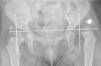

The radiologic followup consisted of anteroposterior pelvis radiographs and axial hip radiographs. In cases treated with spica casts or with a high degree of hip instability, the followup also included a computed axial tomography scan in the early postoperative period to confirm the correct reduction of the dislocated hip. The radiographic parameters that were documented were the location of the ossification centre in the femoral head based on the Ombredanne quadrants (Fig. 1) and the AI before and after orthopaedic treatment. These values were measured in digital radiographs using the Centricity application developed by General Electrics.

As for the position of the centres of ossification before treatment, they were located in the lower inner quadrant in four cases, in the lower outer quadrant in eight cases, and in the upper outer quadrant in four cases. After conservative treatment, the position of the centres had shifted, with ten of them located in the lower inner quadrant and the remaining six in the lower outer quadrant. The hips that were positioned normally at the outset were treated due to the presence of marked acetabular dysplasia, with a mean AI of 38°, as they were not likely to correct spontaneously when the patient started walking.